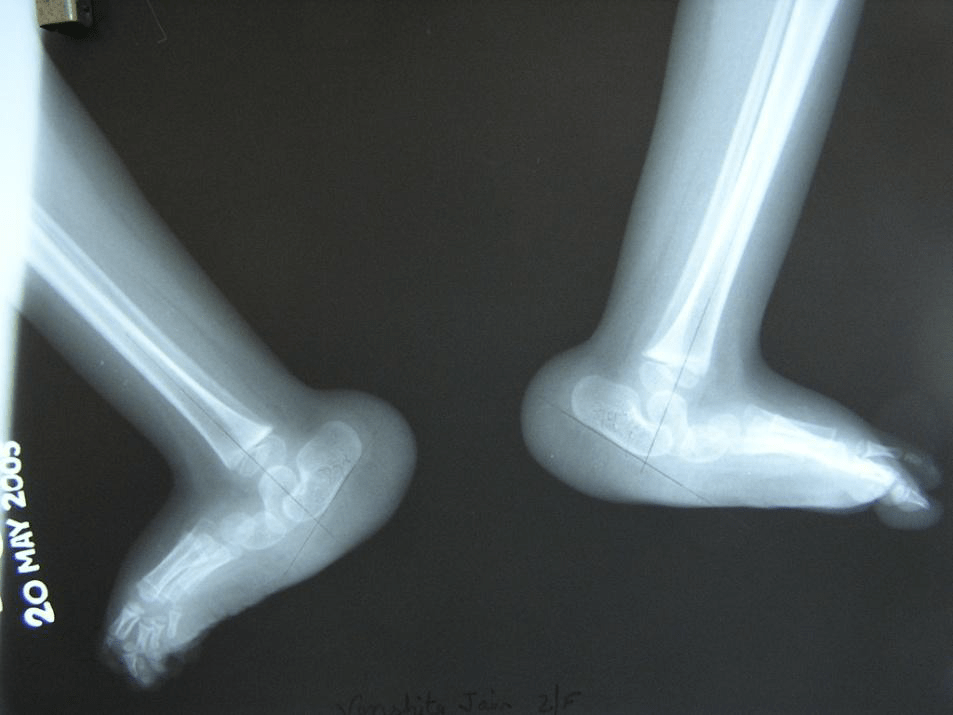

Figure 3 : (top) Lateral views showing ‘vertical talus’ with talo-navicular dislocations on both sides. (bottom) Forced plantar flexion views do not show any change in the talo-calcaneo-navicular relationship.